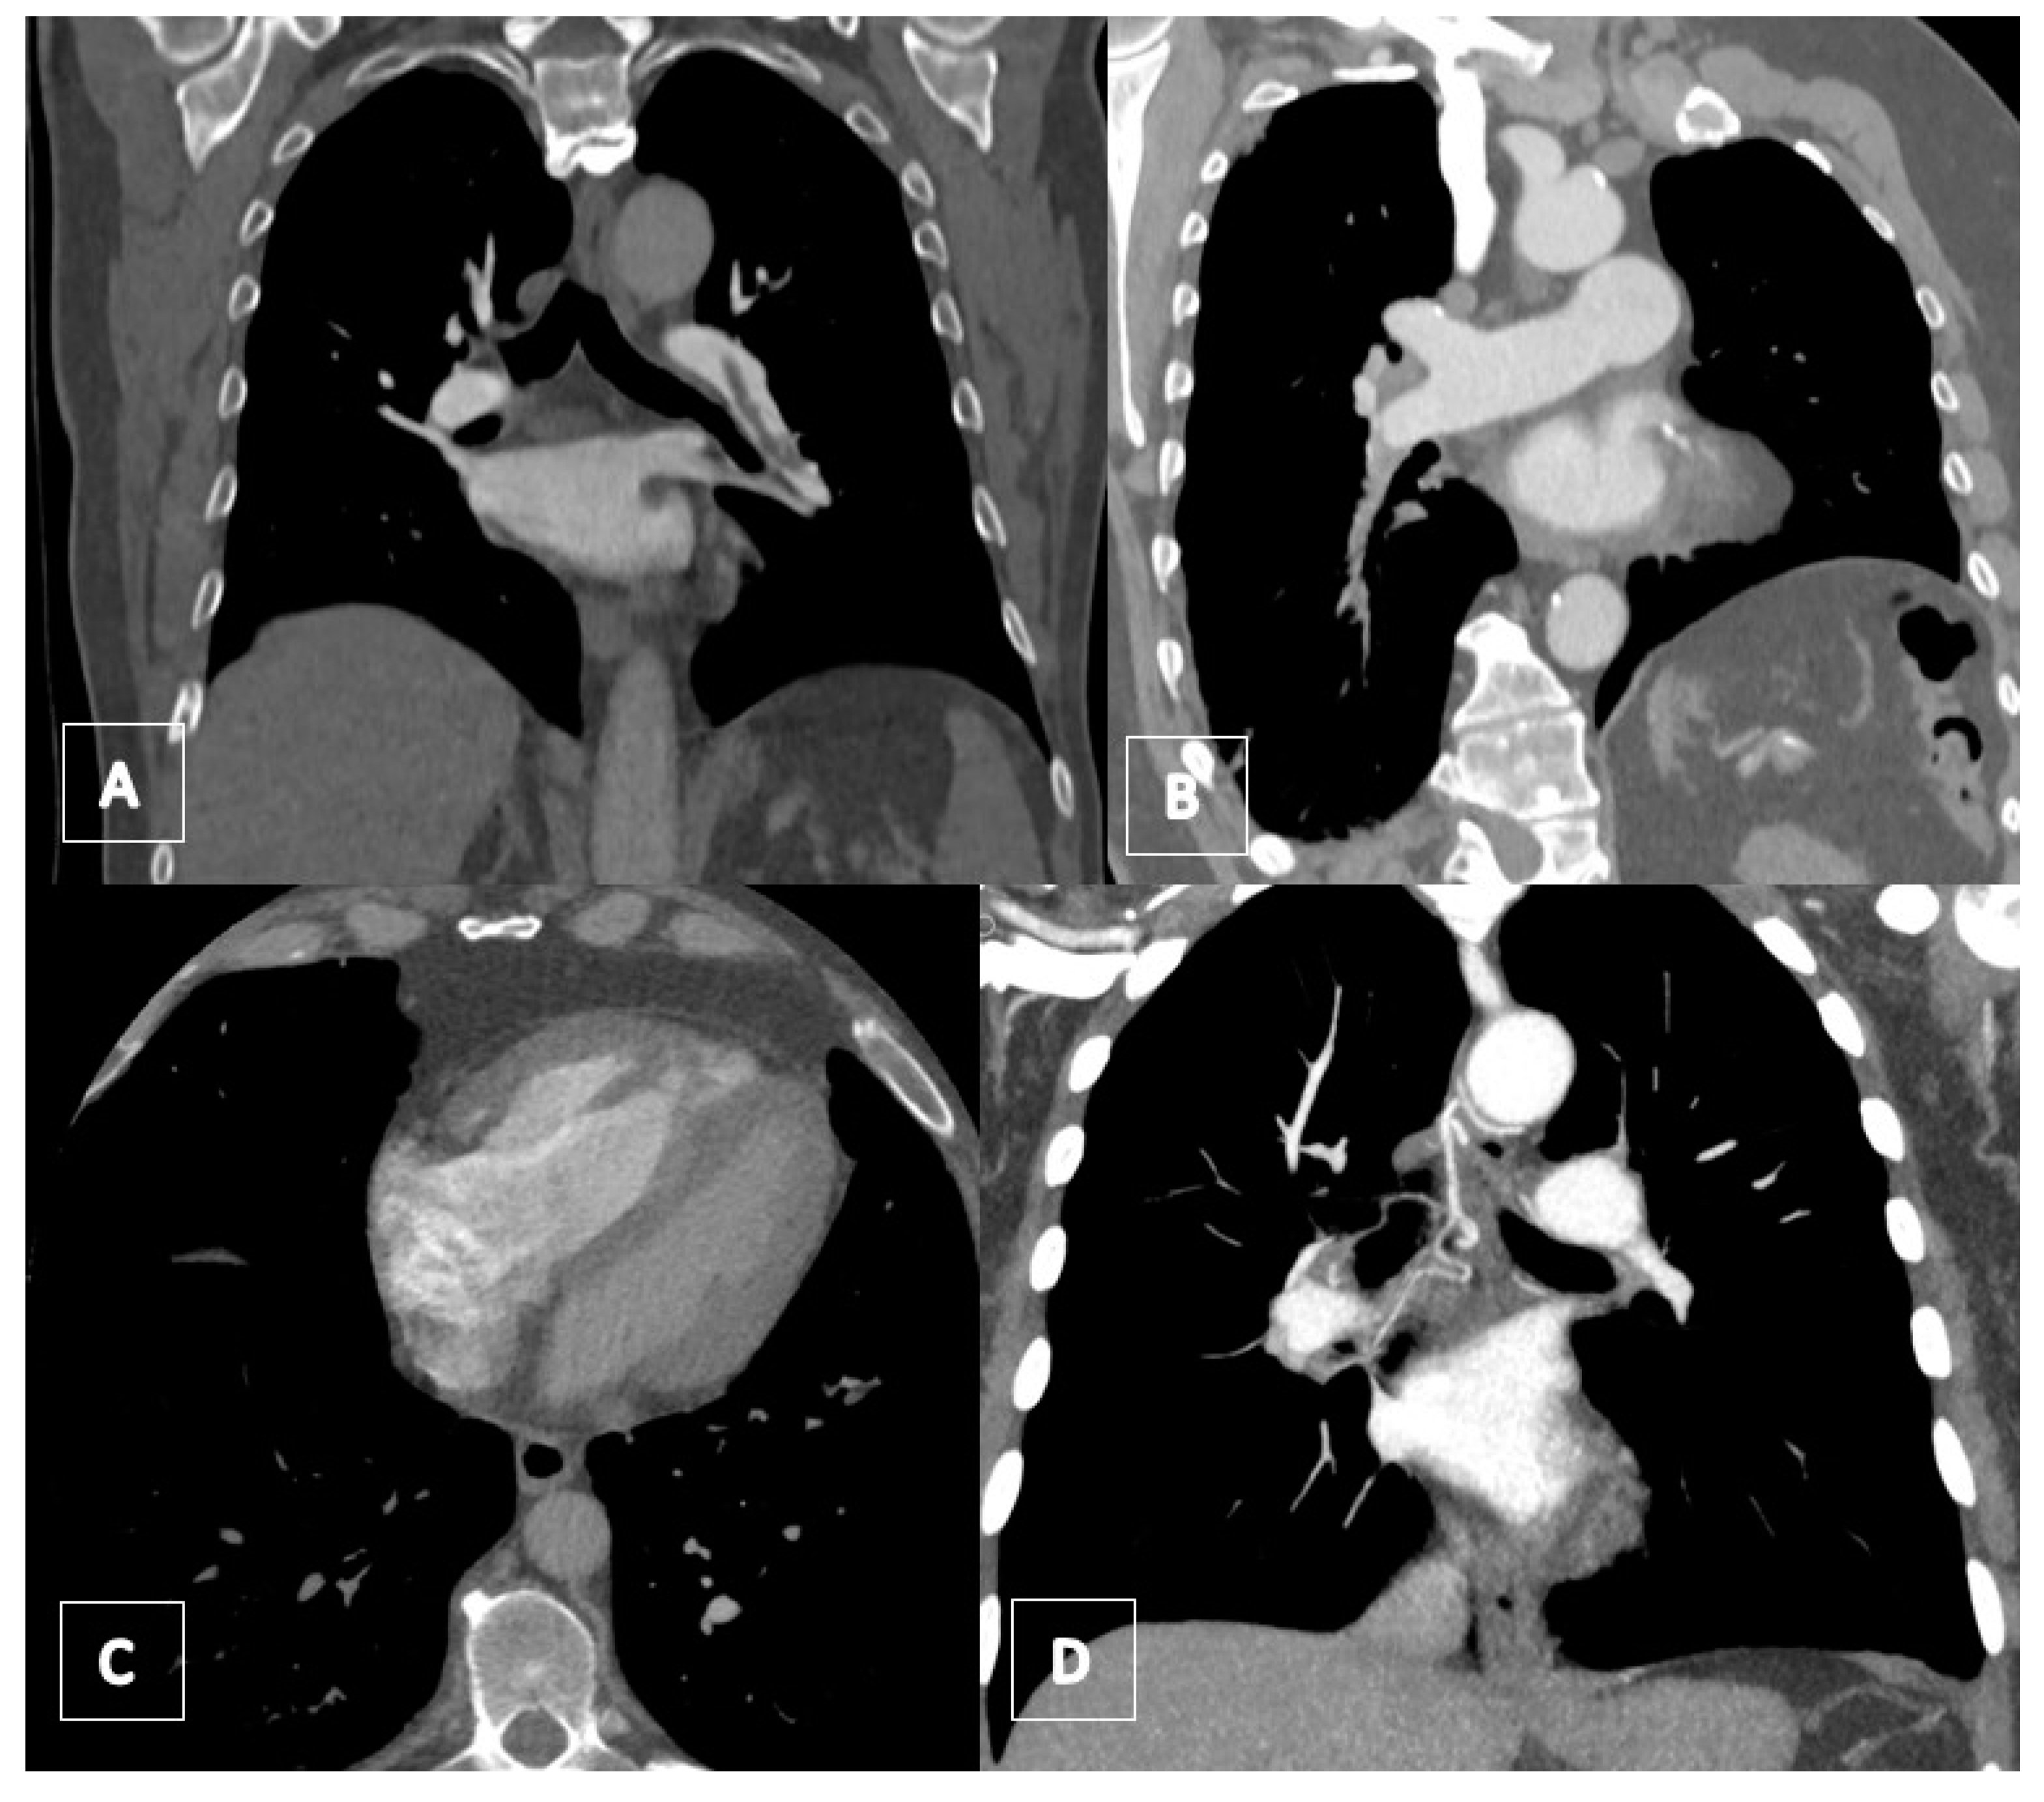

3.4. Computed Tomography Pulmonary Angiography (CTPA)

3.5. Transthoracic Echocardiography